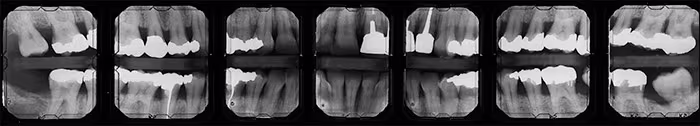

Bitewing Surveys

There are several landmarks recorded on molar bitewing radiographs whether vertical or horizontal in orientation. The most common structures observed are the external oblique ridge and maxillary tuberosity.